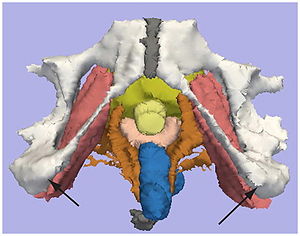

Treatment Planning and Delivery of Whole Brain Irradiation with Hippocampal Avoidance in Rats

Publication: PLoS One. 2015 Dec 4;10(12):e0143208. PMID: 26636762 | PDF Authors: Cramer CK, Yoon SW, Reinsvold M, Joo KM, Norris H, Hood RC, Adamson JD, Klein RC, Kirsch DG, Oldham M. Institution: Department of Radiation Oncology, Duke University Medical Center, Durham, NC, USA. Background/Purpose: Despite the clinical benefit of whole brain radiotherapy (WBRT), patients and physicians are concerned by the long-term impact on cognitive functioning. Many studies investigating the molecular and cellular impact of WBRT have used rodent models. However, there has not been a rodent protocol comparable to the recently reported Radiation Therapy Oncology Group (RTOG) protocol for WBRT with hippocampal avoidance (HA) which is intended to spare cognitive function. The aim of this study was to develop a hippocampal-sparing WBRT protocol in Wistar rats. Methods: The technical and clinical challenges encountered in hippocampal sparing during rat WBRT are substantial. Three key challenges were identified: hippocampal localization, treatment planning, and treatment localization. Hippocampal localization was achieved with sophisticated imaging techniques requiring deformable registration of a rat MRI atlas with a high resolution MRI followed by fusion via rigid registration to a CBCT. Treatment planning employed a Monte Carlo dose calculation in SmART-Plan and creation of 0.5 cm thick lead blocks custom-shaped to match DRR projections. Treatment localization necessitated the on-board image-guidance capability of the XRAD C225Cx micro-CT/micro-irradiator (Precision X-Ray). Treatment was accomplished with opposed lateral fields with 225 KVp X-rays at a current of 13mA filtered through 0.3 mm of copper using a 40x40 mm square collimator and the lead blocks. A single fraction of 4Gy was delivered (2Gy per lateral field) with a 41 second beam on time per field at a dose rate of 304.5 cGy/min. Dosimetric verification of hippocampal sparing was performed using radiochromic film. In vivo verification of HA was performed after delivery of a single 4Gy fraction either with or without HA using γ-H2Ax staining of tissue sections from the brain to quantify the amount of DNA damage in rats treated with HA, WBRT, or sham-irradiated (negative controls). Results: The mean dose delivered to radiochromic film beneath the hippocampal block was 0.52Gy compared to 3.93Gy without the block, indicating an 87% reduction in the dose delivered to the hippocampus. This difference was consistent with doses predicted by Monte Carlo dose calculation. The Dose Volume Histogram (DVH) generated via Monte Carlo simulation showed an underdose of the target volume (brain minus hippocampus) with 50% of the target volume receiving 100% of the prescription isodose as a result of the lateral blocking techniques sparing some midline thalamic and subcortical tissue. Staining of brain sections with anti-phospho-Histone H2A.X (reflecting double-strand DNA breaks) demonstrated that this treatment protocol limited radiation dose to the hippocampus in vivo. The mean signal intensity from γ-H2Ax staining in the cortex was not significantly different from the signal intensity in the cortex of rats treated with WBRT (5.40 v. 5.75, P = 0.32). In contrast, the signal intensity in the hippocampus of rats treated with HA was significantly lower than rats treated with WBRT (4.55 v. 6.93, P = 0.012). Conclusion: Despite the challenges of planning conformal treatments for small volumes in rodents, our dosimetric and in vivo data show that WBRT with HA is feasible in rats. This study provides a useful platform for further application and refinement of the technique. Funding:

MRI with labeled structures from atlas registered to the CBCT. Registration was carried out with the open source imaging tool 3D Slicer, Version 4.4.0. |